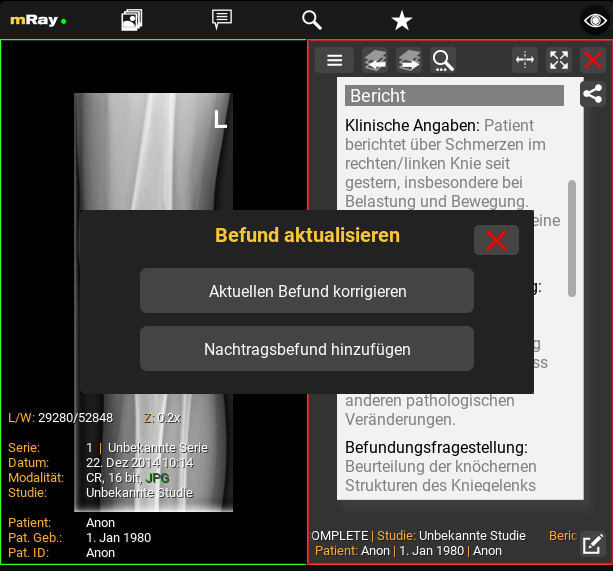

12.6. Corrective and Supplementary Report

Approved reports cannot be modified; however, it is possible to create a corrective or supplementary report. These reports are versioned, ensuring that the original approved report remains unchanged.

To create a corrective or supplementary report, click the Edit button located at the bottom right corner of an approved report. You will then be prompted to select the type of report you wish to create.

12.6.1. Corrective Report

A corrective report allows a complete modification of the text of an already approved report.

12.6.2. Supplementary Report

A supplementary report permits the addition of new information to the report, but only once. The existing text remains unmodifiable.